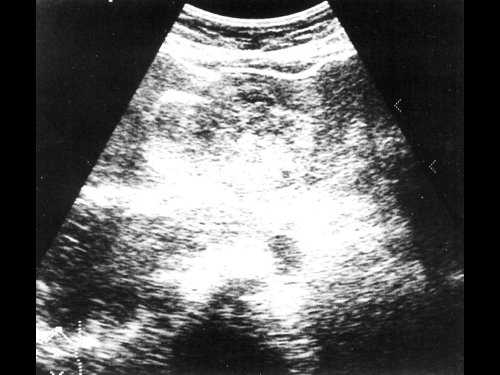

Если ультразвуковые признаки достаточно типичны, пациенты с асимптоматичной гемангиомой и отсутствием риска малигнизации могут проходить повторные обследования с интервалом в 3-6 месяцев. У пациентов с риском малигнизации ситуация более сложная. В частности, гипоэхогенный ореол вокруг повреждения более соответствует метастазам, чем гемангиоме [15]. У большинства гемангиом имеется гиперэхогенный ободок по периферии, но нет периферического ореола или боковой тени. Так как гепатоцеллюлярная карцинома и метастазы рака толстой кишки, опухоли островковых клеток, карциноида, хориокарциномы могут манифестировать ультразвуковыми признаками, идентичными таковым при гемангиоме, ультразвуковое исследование не может быть единственным достоверным методом дифференциальной диагностики гемангиомы и рака. Поэтому для более точной диагностики необходимо проведение компьютерной томографии с контрастированием, радионуклидные исследования с мечеными эритроцитами, либо ядерно-магнитный резонанс.

В связи с тем, что неосложненные гемангиомы состоят из заполненных кровью сосудистых полостей, при стандартной компьютерной томографии они определяются как хорошо очерченные гомогенные образования, идентичные по плотности внутрипеченочным сосудам, и пониженной плотности по отношению к печеночной паренхиме [16]. Очаги пониженной по сравнению с кровью плотности могут быть видны внутри гемангиомы и представлять собой участок внутреннего фиброза. В печени с жировой инфильтрацией гемангиомы при компьютерной томографии выглядят гиперэхогенными, затрудняя тем самым точную оценку их структуры.

Компьютерные томограммы гемангиом после введения внутривенного контраста зависят от кровотока внутри образования и времени визуализации печеночного кровотока. Характерно, что кровь внутри гемангиомы медленно центростремительно течет от периферических синусоидов к центральным. Поэтому динамическая усиленная компьютерная томография с внутривенным контрастированием показывает центростремительное увеличение гемангиомы, плотность которой одинакова с плотностью прилежащих сосудов на том же уровне визуализации.

Общая интенсивность повреждения будет наибольшей по периферии на ранних стадиях введения контраста и уменьшается по мере снижения концентрации йода в кровотоке. Визуализация через 30 минут после введения контраста показывает изоэхогенность гемангиомы и окружающей печеночной паренхимы. Визуализация во время печеночной артериальной фазы внутривенного контрастирования (25-50 с после введения контраста) дает ярко выраженные пристеночные очаги по периферии гемангиомы. Эти узлы, считающиеся питающим сосудистым центром гемангиомы, характерны в диагностическом плане для гемангиом [18,19].

В нашем случае при ультразвуковом исследовании брюшной полости выявлено атипичное строение гемангиомы, динамическая компьютерная томография указывает на типичную гемангиому (рис. 2а, б). При этом важно знать, что только приблизительно в 54% случаев у больных с гемангиомами имеет место характерная перфузия с центростремительным усилением и поздним заполнением [20]. Однако в связи с тем, что этот тип усиления встречается только у 1,6% первичных и вторичных злокачественных опухолей печени, определение структуры данного усиления позволяет уверенно дифференцировать гемангиомы от злокачественных печеночных опухолей [20].